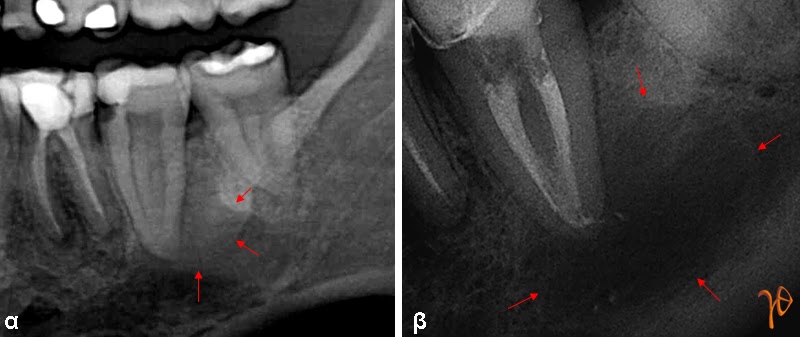

Οι πιο συχνές βλάβες στο στόμα είναι τα αποστήματα, τα οποία όταν οφείλονται σε μικροβιακές λοιμώξεις δοντιών της άνω γνάθου μπορούν να εκδηλώνονται και στην υπερώα (Εικόνα 3). Η θεραπεία τους προϋποθέτει την θεραπεία του υπεύθυνου δοντιού.

Εικόνα 3. α. Απόστημα που οφείλεται σε γομφίο οδόντα (βέλος), β. Απόστημα που οφείλεται σε τομέα οδόντα (βέλος).